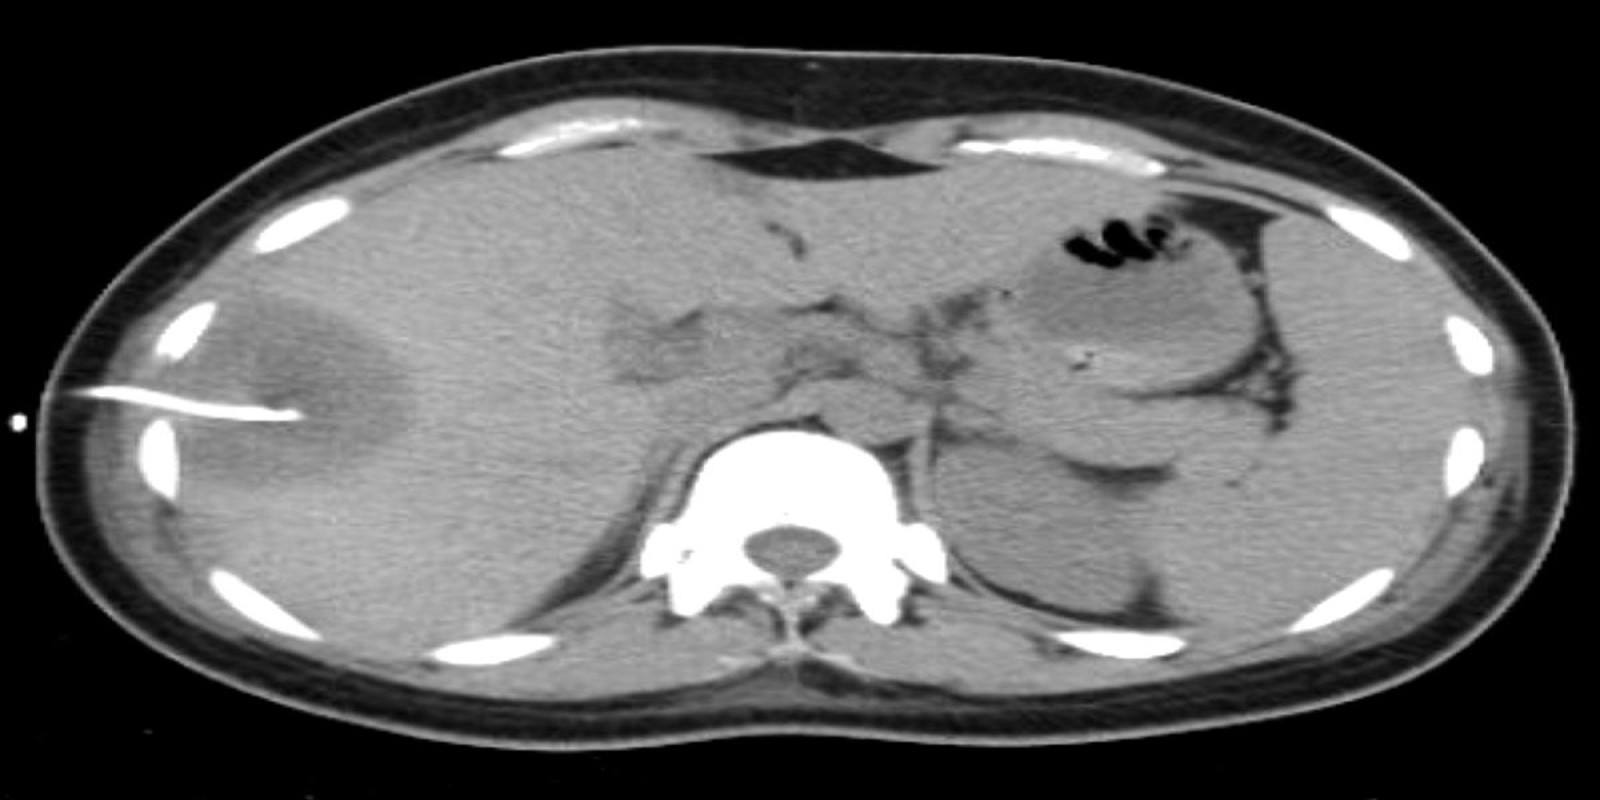

Caso Código 247A de Abscesso Hepático

Cod.: 247A